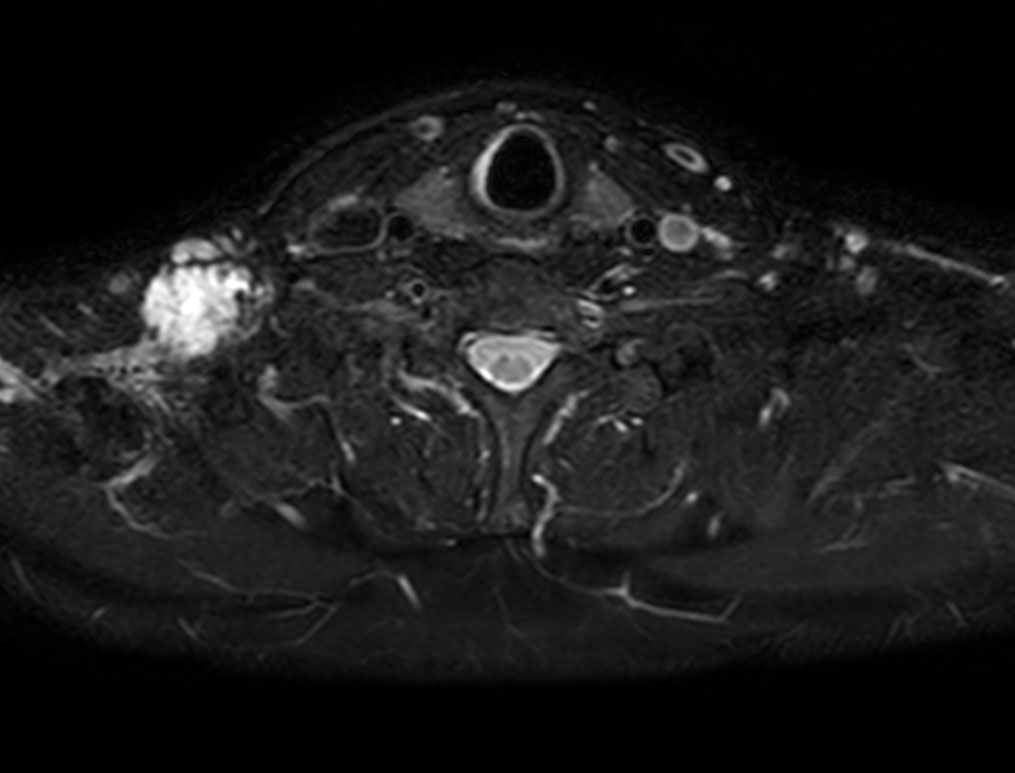

Axial T2w mDIXON XD TSE (Water only)